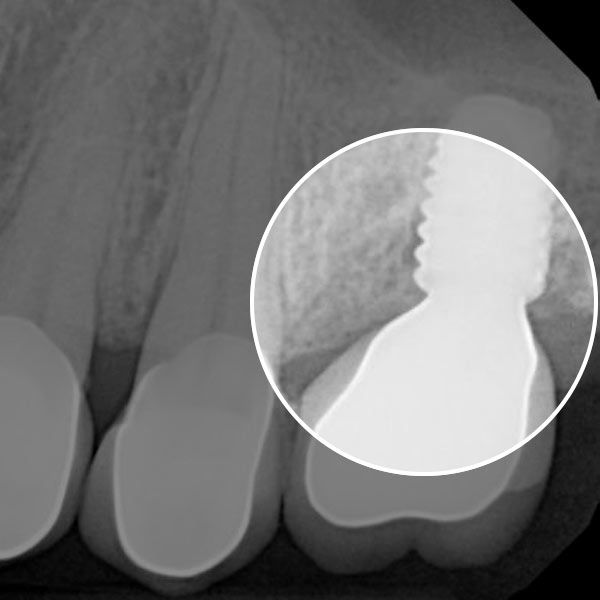

See the Difference LAPIP CAN MAKE

Dental implant revision surgery is a complex procedure which can cost upwards of $3,000. The LAPIP protocol is the only FDA-approved treatment for avoiding implant failure. The final cost of LAPIP will depend on several factors, such as the number of appointments you need and how many dental implants require treatment. While insurance does not generally cover treatment with LAPIP, the cost of this procedure is significantly less than replacing a failed implant.

Before the LAPIP protocol, the most common treatment for severe implant failure was removal and replacement of the restoration. The process for replacing a failed implant is complicated and requires multiple treatments, including implant removal, a bone graft, and placement of a new implant. Typically, a new restoration is needed as well. In less complex cases, conventional treatment can focus on removing damaged tissue but this option still requires several appointments and follow-ups. In contrast, treating peri-implantitis with LAPIP typically requires only one visit and can save you time and money.

Peri-implantitis is a serious condition which can threaten the stability of your smile. The best way to find out if you qualify for the innovative LAPIP protocol is to schedule an appointment with a dentist.